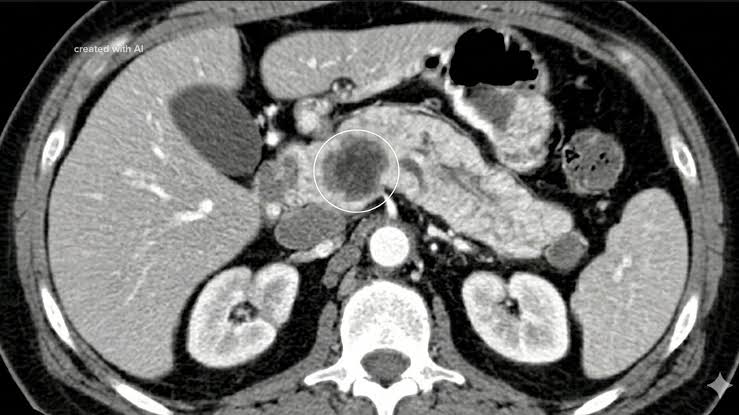

Mayo Clinic announces breakthrough in early cancer detection

ROCHESTER, Minn. — Minnesota's world-renowned Mayo Clinic continues to live up to its reputation for achieving medical miracles, announcing Wednesday it has...